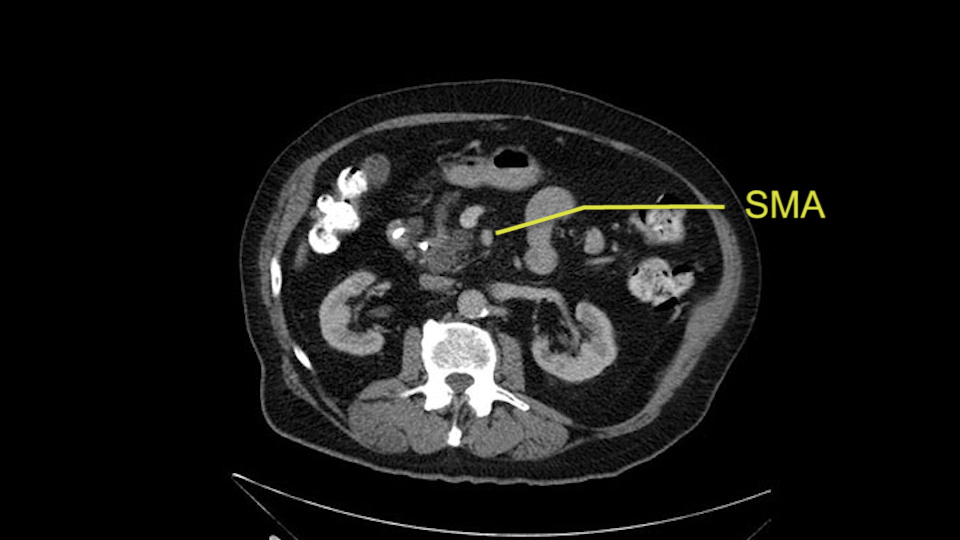

Then either through the coronal or the axial, I’ll do both. Look at the SMA -which is here- I had already looked at it and I don’t see any involvement. There’s the SMA with a nice fat plane between the SMA and the tumor. Over here you can see on the axial, there’s the SMA. Everything on the right side of the SMA has got some nice black around it, which is fat, which means probably no tumor [no tumor, no tumor]. Follow it up to the origin, coming off the aorta. So those are the two technical things that I worry about: the SMA and the SMV.